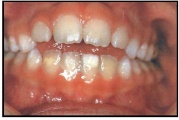

kahepoolse lõhega lapse hambumus

Valehambumus

Hammaste asendianomaaliad on tingitud tavaliselt arenguhäirest.